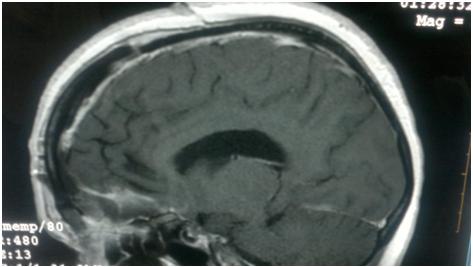

A  50 year old female presented to us in emergency with complaints of episodes of seizures and headache for  past few days . MRI brain done at a private institution revealed large olfactory grove meningioma measuring approximately 10 x 12 centimeters in size. Tumor was successfully removed by Dr Vineet Saggar after eight hours of  marathon surgery and patient was discharged after few days without any neurological deficit.

Pre Operative MRI of the Patient showing  large tumour

Post operative MRI showing complete tumor removal